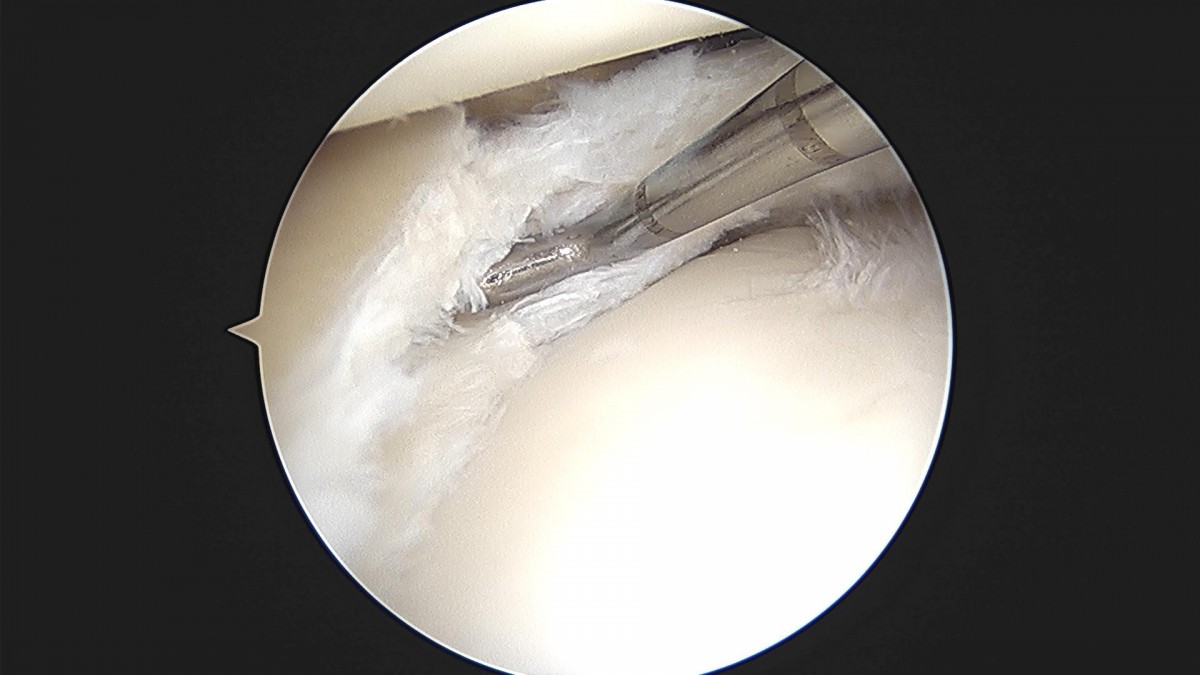

배우한원장님 무릎 내측 반월상 연골판 절제술 김도O 환자

bccafb0c4c611c3a9fcb6ca752df8d40_1670487534_872.jpg